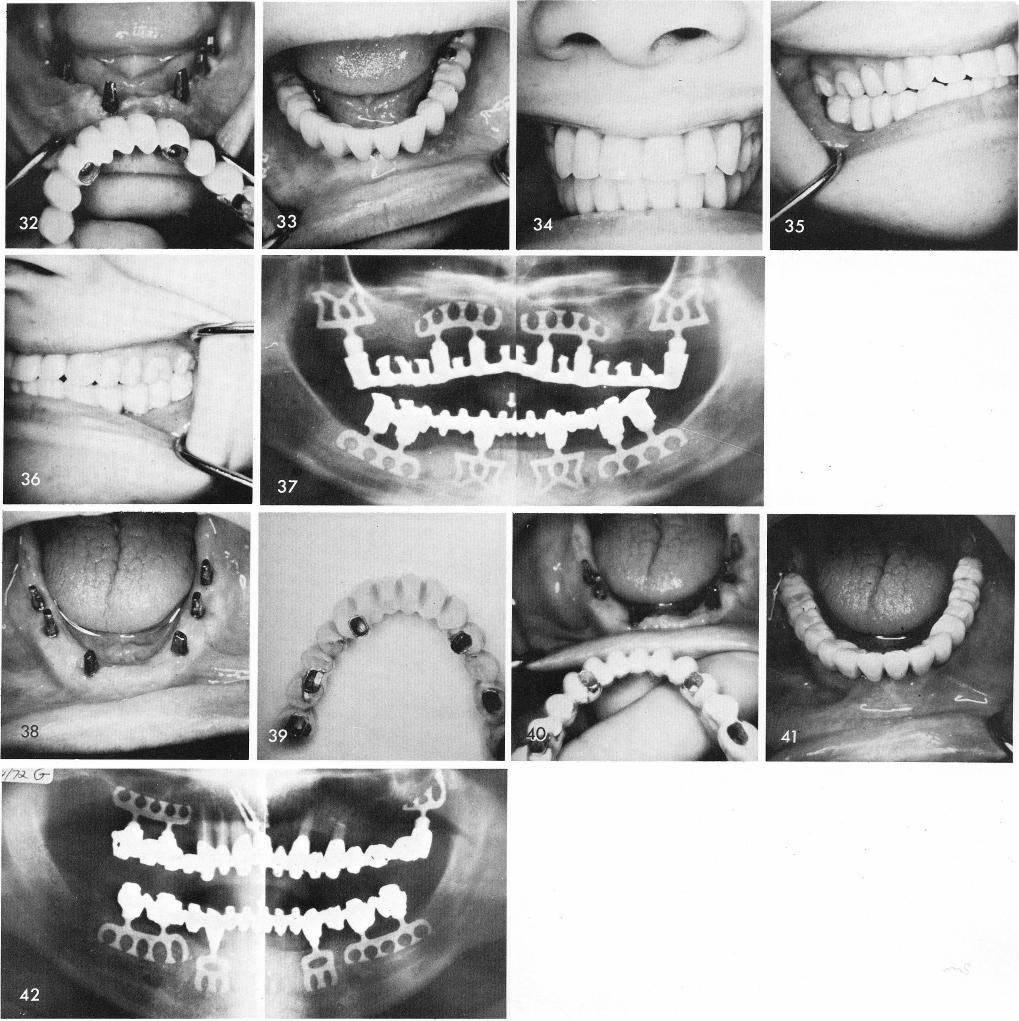

fig. 31, are ready to accept the full arch fixed restoration, figs. 32, 33, 34, 35, 36. A final x-ray, fig. 37. The case is extremely successful after seven and one half years.

The blade posts should be symmetrically placed whenever possible. This case also reveals the two cuspid blade posts to be narrow mesio-distally to allow for better esthetics, fig. 38. Notice also, how far out labially the anterior teeth must often be made to prevent the lips from falling in, fig. 39. Figs. 40 and 41 show the cementation of the restoration. Fig. 42 shows the post-operative x-ray.